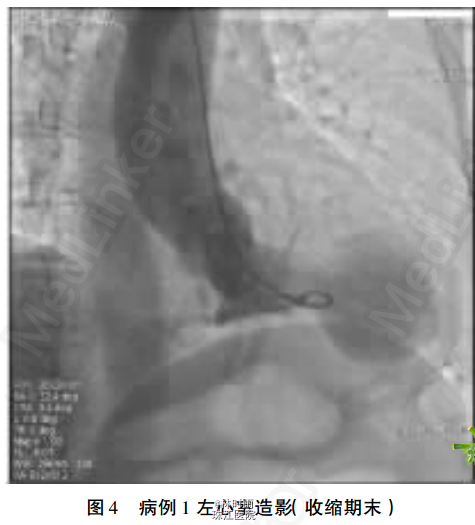

初步诊断——冠心病:急性下壁心肌梗死。(结合患者年龄等多种冠心病危险因素、临床症状及心电图改变,考虑患者冠心病、急性下壁心肌梗死可能)。 处理——患者入院至症状发作4h,故行急诊冠脉造影,结果显示冠脉未见明显狭窄病变,行左心室造影,提示典型心尖球囊样综合征改变(见图3-4)。 住院期间监测患者心肌酶学指标均轻度升高,且酶学峰值不符合心肌梗死特点,肌钙蛋白T(cTnT)于发病72h基本恢复正常水平。另予β阻滞剂治疗。 确定诊断——心尖球囊样综合征。

术后1周复查超声心动图显示左室整体室壁运动协调。心尖球囊样综合征大部分病人发病前有心理或躯体等相关应激因素,而后出现类似急性心肌梗死的临床表现,但冠脉造影无器质性狭窄病变。 符合一支以上冠脉供血区域的室壁运动障碍,因其左室造影收缩期的形态显示底部圆形、颈部细窄呈气球样,故称为心尖球囊样综合征,又称为Tako-Tsubo 综合征、 应激性心肌病及一过性左室功能不全综合征。 日本报道有1%-2%的临床表现与AMI相似的病人最后被确诊为本病,而绝经后女性所占比例较高。 本病预后相对良好,关于其诊断亦无统一标准,有学者总结归纳的诊断标准为: ①主要标准:可逆性左心室心尖部球囊样运动异常伴基底部过度收缩,心电图改变类似于AMI; ②次要标准:情绪等诱发,临床有胸痛、 胸闷等症状,伴有心肌酶学指标升高。本患者为绝经后女,发病前有明确的情绪应激诱因,发作时心电图均表现为下壁、 前壁及侧壁导联的T高尖、ST段抬高,继而多导联T波明显倒置,不符合单一冠脉供血区心肌梗死心电图导联改变;心肌酶谱的动态变化特点亦不同于AMI;1周内左心室心肌运动明显改善。 本研究病例心肌酶升高,但升高峰值相对心肌梗死峰值低,与超声心动图的大面积室壁运动障碍不相符,酶学升高曲线与心肌梗死不同,且 7天后仍未恢复正常,均符合心尖球囊样综合征临床特点。【转载自:《临床和实验医学杂志》2013年3月第12卷第5期,《心尖球囊样综合征2例报告》】